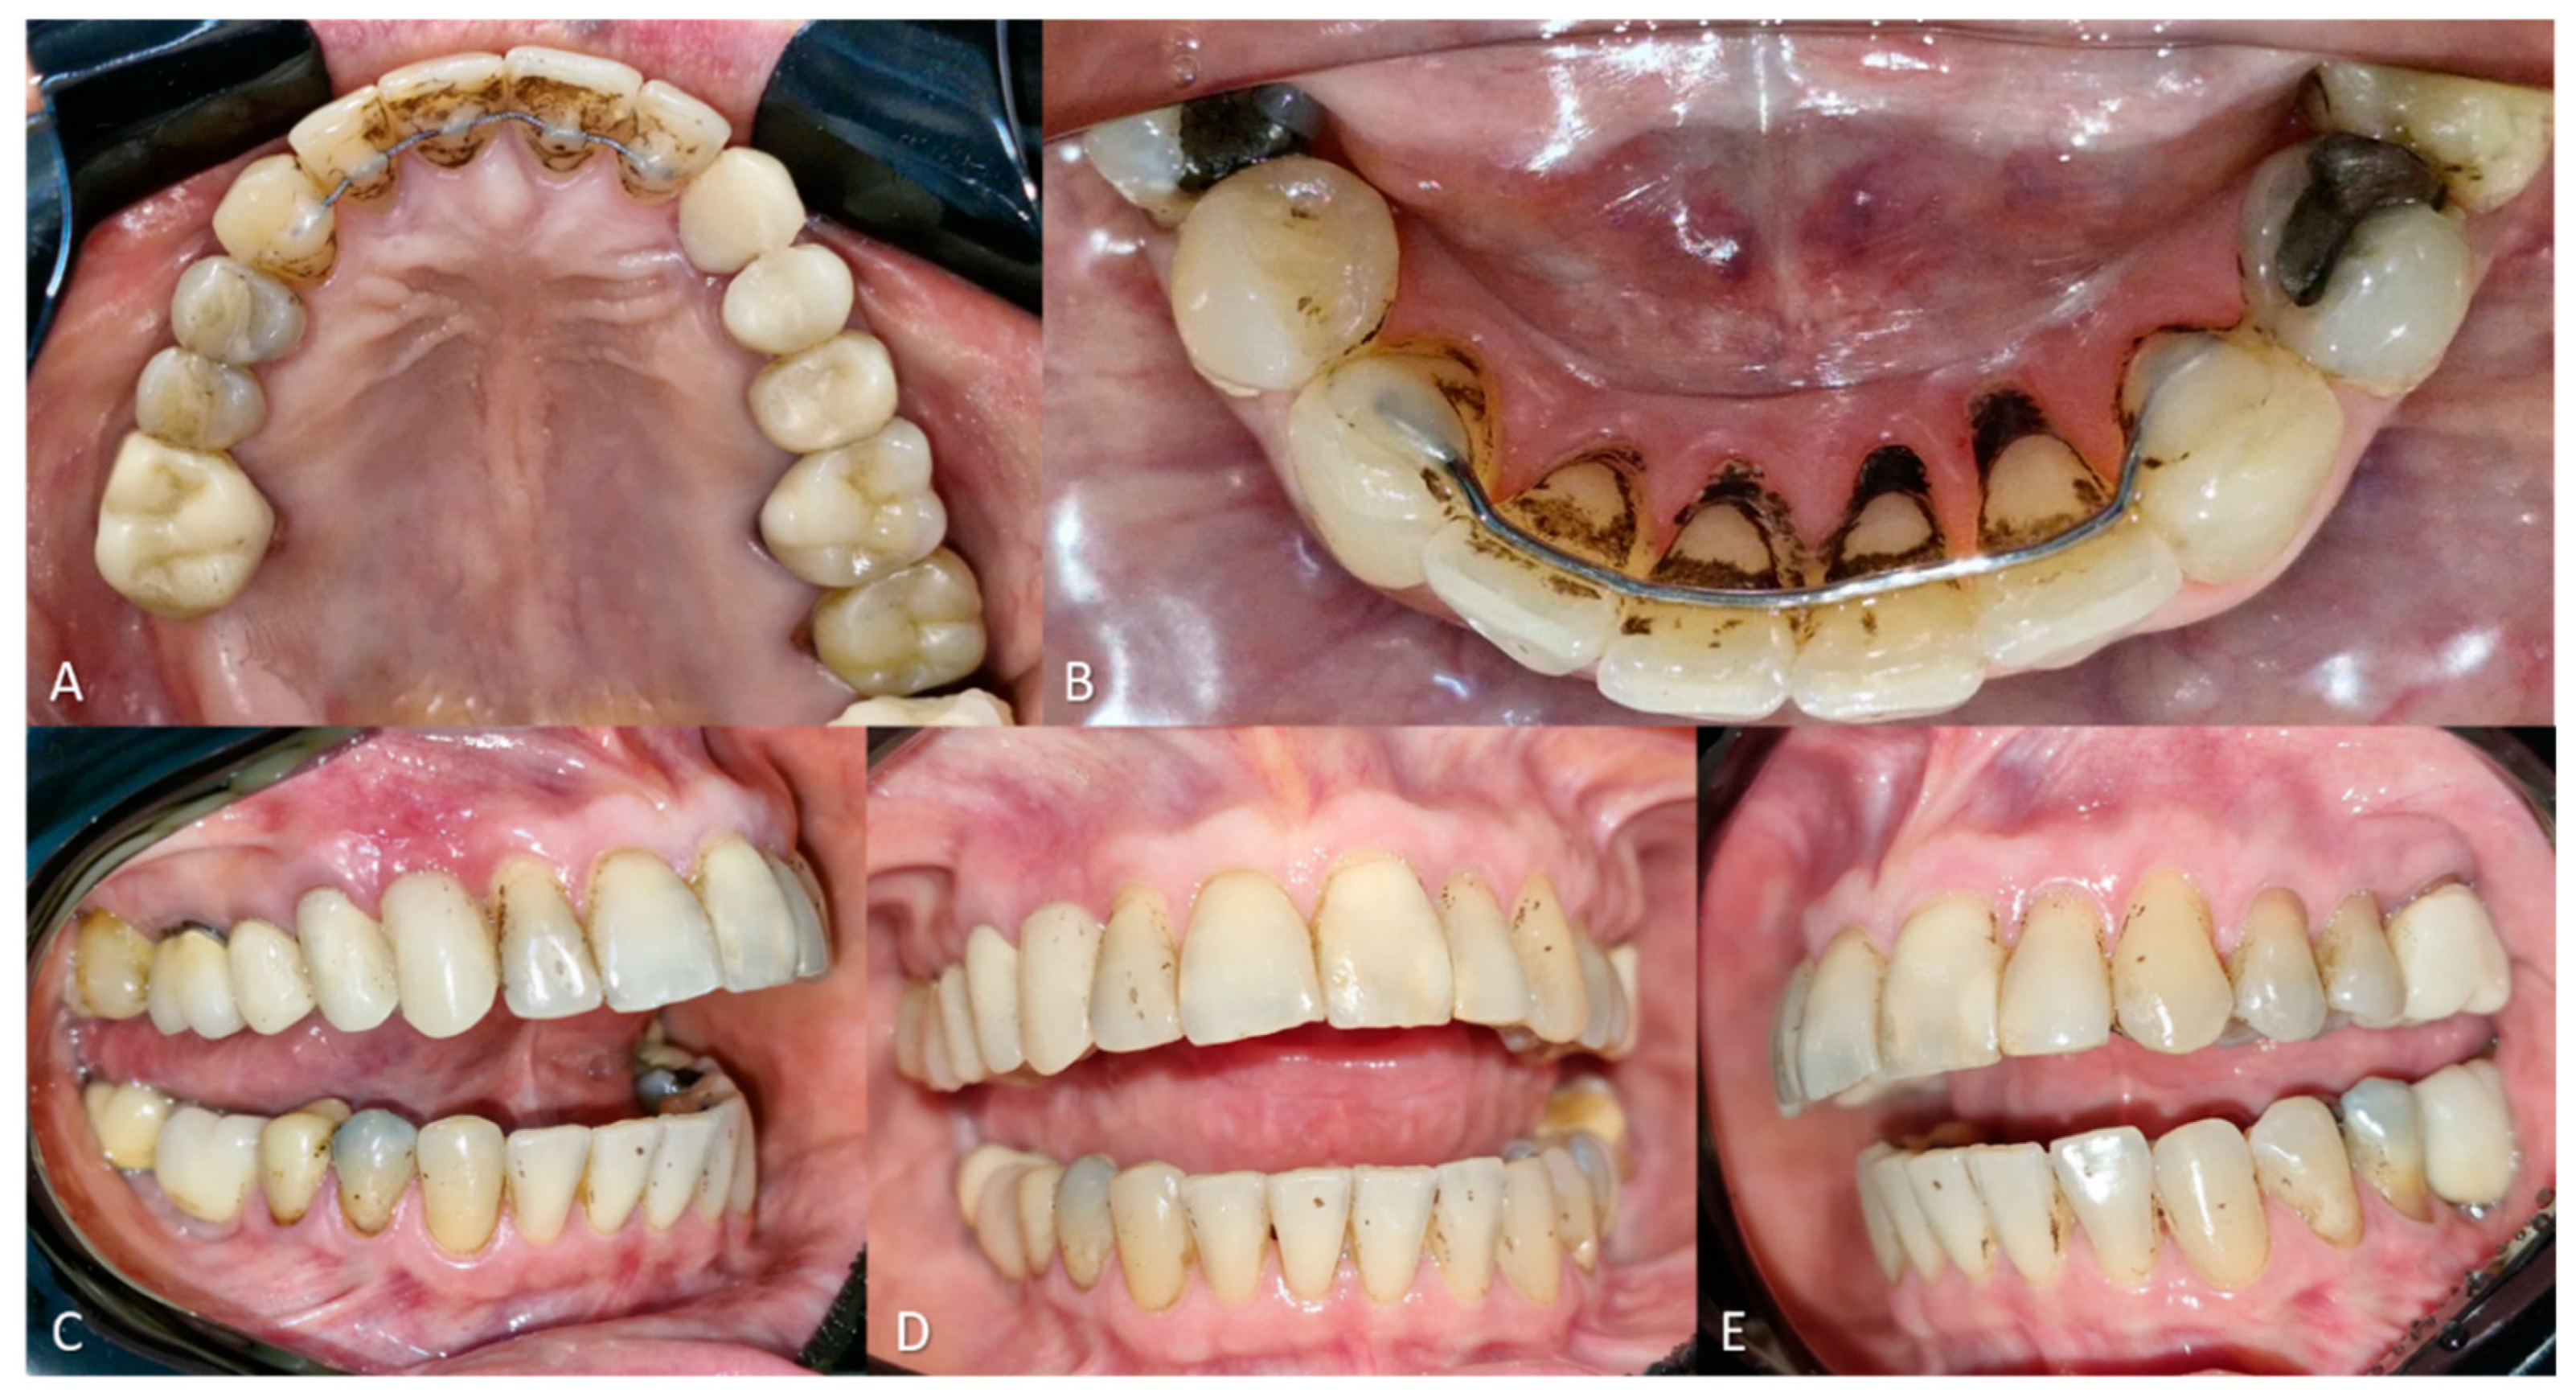

According to the patient, the black stains had appeared two years prior, initially affecting the buccal surfaces of the teeth, compromising esthetics and self-esteem. She mentioned undergoing ultrasonic scaling one month before the consultation, which partially removed the buccal stains but caused considerable dentin hypersensitivity. Intraoral examination revealed a Black Stain score of 3, according to the Gasparetto classification, with stain presence across the palatal surfaces of the maxillary and mandibular incisors, in addition to multiple stains distributed across the buccal surfaces of most teeth (Figure 4).

Figure 4. (A–E) Initial clinical presentation. Presence of extrinsic black stains on the buccal and lingual surfaces of all teeth.